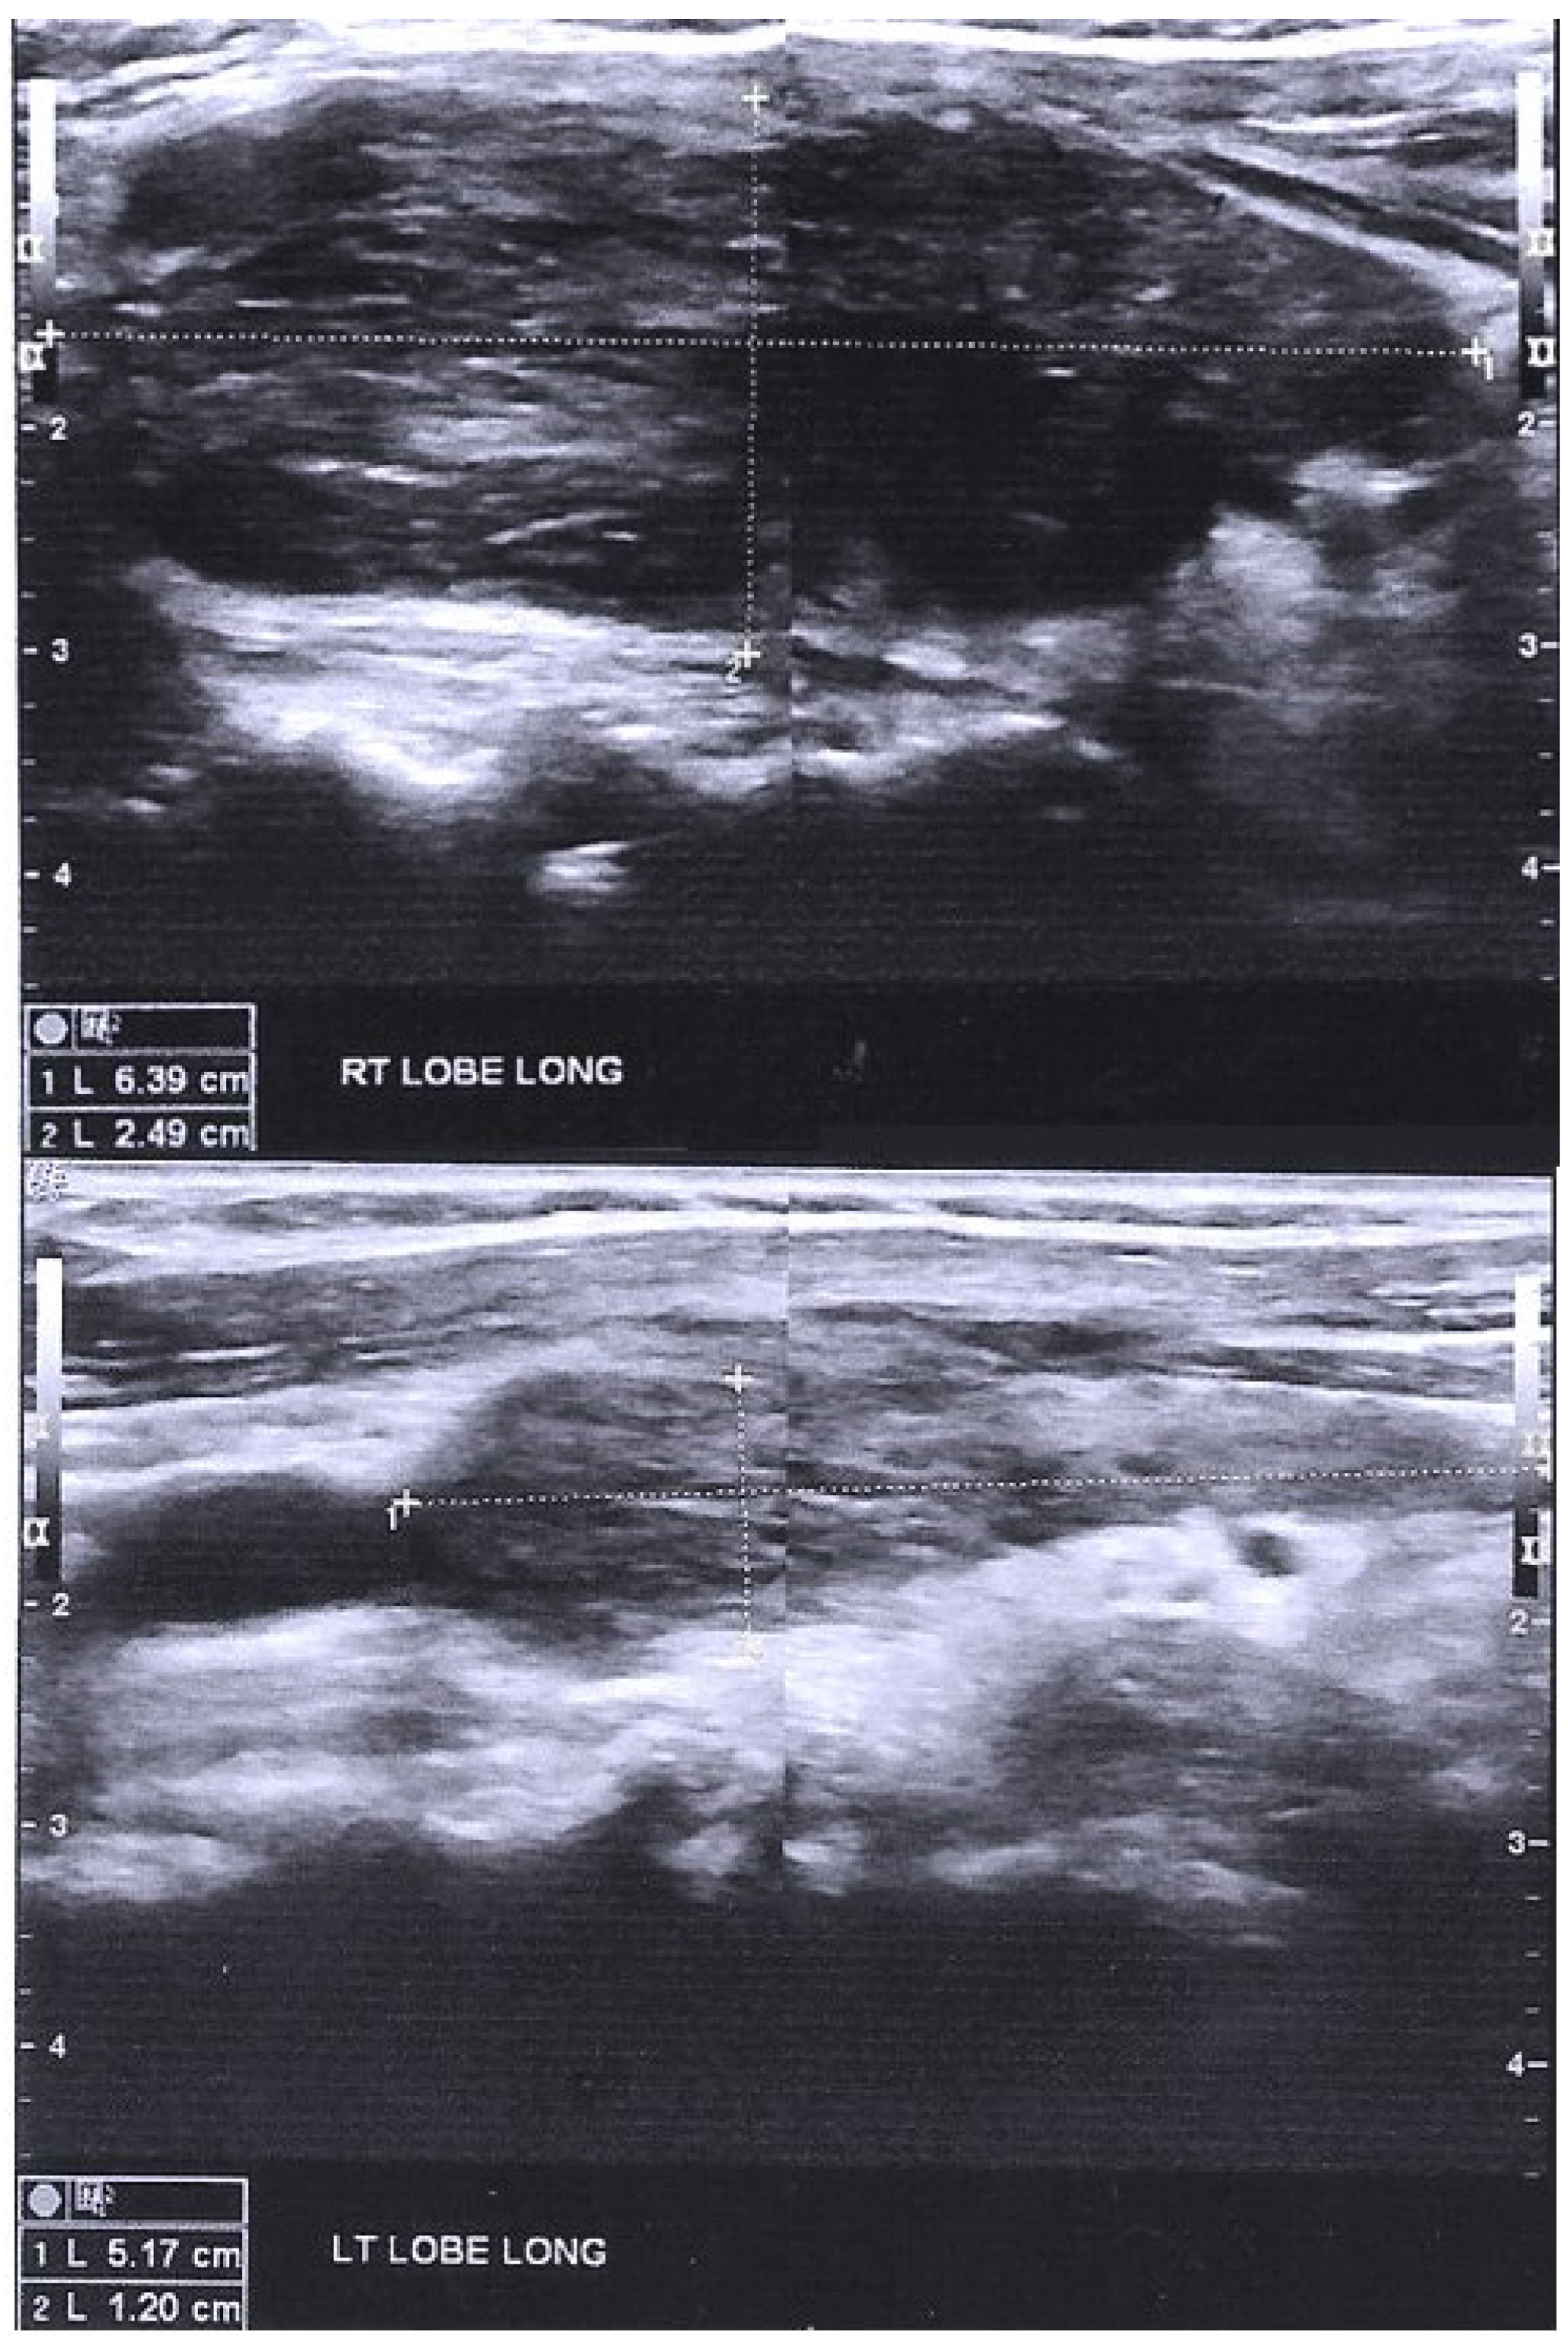

2.1. Case 1

2.2. Case 2